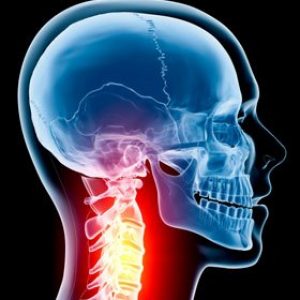

Но не само това, една от най-често лекуваните области включва гръбначния стълб (врата, гръдния кош, кръста ).